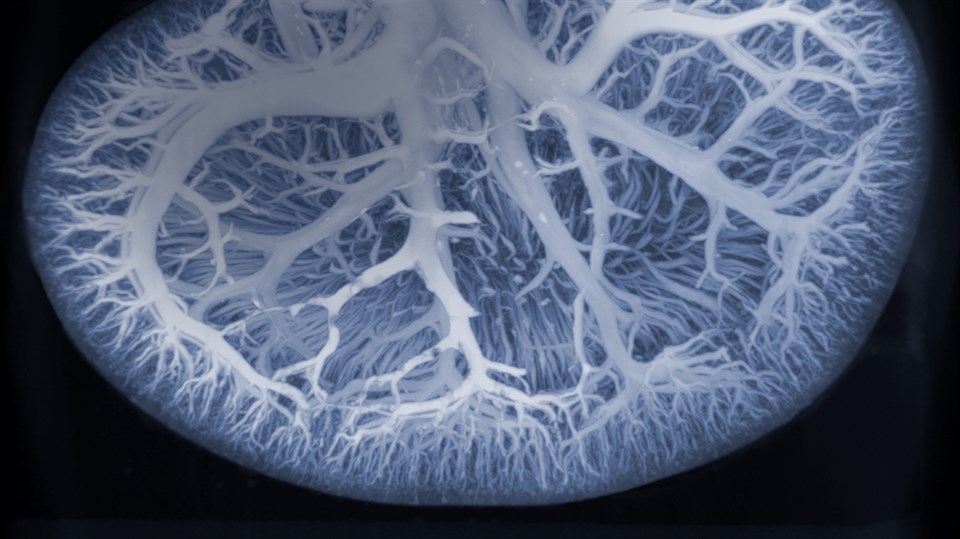

Diagnostic Imaging is focused on biomedical imaging, particularly translation between preclinical models and clinic. Specific research areas include biomedical imaging and biosignal analysis, MR and ultrasound imaging, radioisotopes and nuclear medicine, medical imaging computing. Below we have included examples of our activities in research related to Diagnostic Imaging.